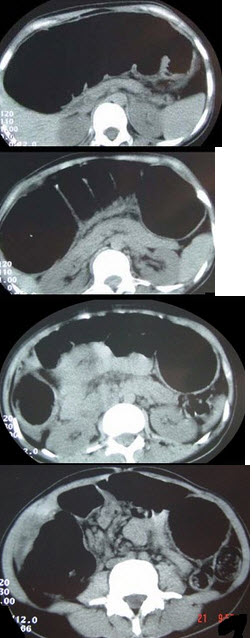

女,30岁,便秘、腹痛腹胀多年,CT检查如图,最可能的诊断是( )

A:结肠肠梗阻

B:先天性巨结肠

C:结肠肠套叠

D:结肠肠扭转

E:结肠肠栓塞